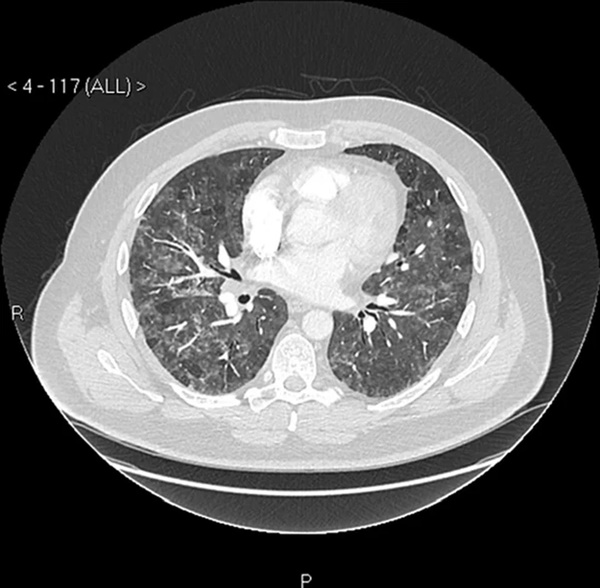

Do không thể chịu nổi tình trạng này nữa, Martin quyết định tới bệnh viện kiểm tra. Qua kết quả chụp X-quang, trên phổi của Martin có nhiều đốm và bác sĩ cảnh báo rằng, anh đang thở một cách rất khó khăn. Tuy nhiên, các bác sĩ vẫn chưa thể tìm ra được vấn đề mà Martin đang gặp phải là gì.

Ảnh minh họa